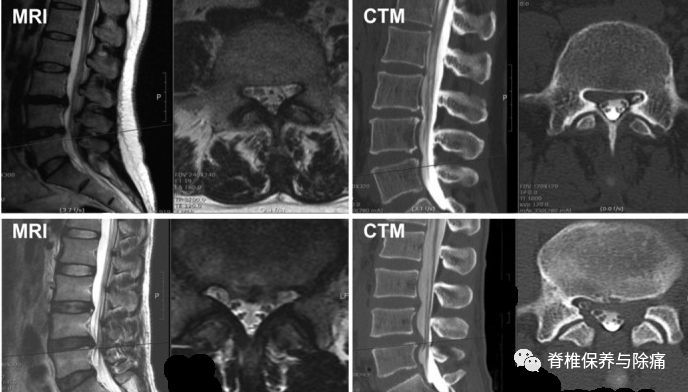

术前症状侧的神经根的轴位MRI和CTM扫描,根据严重程度病理程度分为四级0级:没有神经根受压(根映像是可视化); I级:神经根被激惹;II级:神经根移位或变形;III级:确定的神经根被压缩。

The root imageson the preoperative axial MRI and CTM scans of the symptomatic side at thepathological level were classified into four grades according to the severityof nerve root compression by modifying a previous grading system as follows:grade 0, no nerve root compression (root image is well visualized); grade I, nerveroot is abutted or contacted; grade II, nerve root is displaced or deformed;and grade III, definite root compression or completely nonvisualized (flattenedor obliterated) root image1

突出的髓核和侧隐窝狭窄神经根图像的分级。

A:不激惹神经根(0)级。B:神经根毗邻但不显示任何激惹或变形的迹象(I级)。C:神经根移位,压缩变形(II级)。D:明确的神经根受压的神经根(III级)。E: 侧隐窝无激惹神经根(0)级。F:三侧隐窝三叶草形态变化 (I级)。G: 侧隐窝变尖(II级)。H: 侧隐窝三叶草形缩小, 神经根移位及变形(II级)。I: 侧隐窝夹角变尖, 神经根移位机变形 (II级)。J:严重的侧隐窝夹角变尖,扁平的神经根(III级)。K: 侧隐窝不见神经根(III级)。

Gradingof nerve root images in the herniated nucleus pulposus and lateral recessstenosis. A: No compromise of the nerve root (grade 0). B: The nerve root isabutted but does not show any signs of deviation or deformation (grade I). C:The nerve root is displaced (deviated) and deformed by compression (grade II).D: Definite nerve root compression with the nerve root completely nonvisualized(grade III). E: No compromise of the nerve root in the lateral recess (grade0). F: Trefoil-shape change of the lateral recess (grade I). G: Early acuteangular narrowing of the lateral recess (grade I). H: Trefoil-shape narrowingof the lateral recess, and displaced (deviated) and deformed nerve root (gradeII). I: Angular pinch-like narrowing of the lateral recess, and displaced(deviated) and deformed nerve root (grade II). J: Severe angular pinch-likenarrowing of the lateral recess and flattened nerve root (grade III). K: Theroot image is completely nonvisualized in the lateral recess (grade III).

核磁共振轴位扫描的神经根压分级显示0%为0级,30.8%为I级,38.5%为II级,30.8%为III级。而CTM轴向扫描的神经根压分级显示,0%为0,2.2%为I级,30.8%为II级,67%为III级。从统计学意义上来说,组内和组间平均系数都是显著的差异(表3)。

Gradingof the nerve root compression on the MRI axial scans showed that among thecases, 0% was grade 0, 30.8% were grade I, 38.5% were grade II, and 30.8% weregrade III. On the other hand, grading of the nerve root compression on the CTMaxial scans showed that among the cases, 0% was grade 0, 2.2% were grade I,30.8% were grade II, and 67% were grade III. The mean intraclass coefficientsof both intrarater and interrater reliability were statistically significant(Table 3).

在54%的病例,两个不同的评分结果发现在相同的病人,1个从核磁共振和其他的从CTM(表4)。使用McNemar检验法的测试CTM与MRI的一致性,结果显示两种诊断方法并没有显示诊断的一致性(p < 0.0001)。CTM比MRI更容易识别出更高等级的神经根受压。

In 54% of the cases, two different grading resultswere found in the same patient, one from MRI and the other from CTM (Table 4). The diagnostic concurrence betweenCTM and MRI grades was confirmed by using McNemar’s test, which revealed thatthe two diagnostic modalities did not show diagnostic concurrence of the studyresults (p<0.0001). CTM tended toidentify higher grades of nerve root compression than did MRI.

A:Preoperative magnetic resonance imaging (MRI) T2 and computedtomography-myelography (CTM) axial scans showing differences in rootcompression finding. While the finding is grade I on the MRI axial scan, thefinding is grade III on CTM. Grade I on MRI generally means less significantradicular pain that does not require surgical intervention. However, grade IIIon CTM generally means severe root compression that requires decompressivesurgery. B: CTM axial scan showing severe left L5 root compression byobliteration of the nerve root not detectable on MRI axial scan. While grade IIon MRI generally indicates a moderate degree of root compression, grade III onCTM generally means severe root compression that requires decompressivesurgery. Grade III on CTM is congruent with the patients’ clinical symptoms(severe radicular pain with a VAS score of 8).